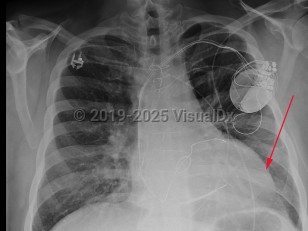

Dilated cardiomyopathy

DCM may have an ischemic or nonischemic etiology. Nonischemic causes include inherited muscular disease, chemotherapy (eg, anthracyclines), endocrinopathies (eg, thyrotoxicosis, pheochromocytoma), infiltrative diseases (eg, amyloidosis), alcohol use disorder, and viral myocarditis. Genetic causes include mutations in genes encoding cardiac sarcomere and cytoskeletal proteins. Many cases are idiopathic.

Patients usually present with symptoms of heart failure including dyspnea, edema, orthopnea, and weight gain. Physical examination may reveal signs of acute left ventricular failure, such as S3 gallop, systolic murmur consistent with mitral regurgitation, pleural effusions, jugular venous distension, and/or peripheral edema.